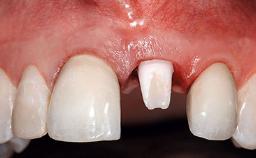

A 32-year-old female Caucasian patient with a compromised maxillary right central incisor was referred to us by a general dentist. Her chief complaints were discomfort and mobility of tooth 11 with unsatisfactory esthetics due to discoloration. The patient reported a previous trauma, some years earlier, as the origin of pathology on the afflicted tooth. Anamnesis was negative for any other dental or periodontal pathology in the remaining dentition. The patient did not take any medication and reported to be a light smoker (5–10 cigs/day). She had high esthetic expectations of her treatment. The extraoral examination revealed a high smile line with full exposure of her maxillary teeth and surrounding soft tissue in the area between the second premolars.